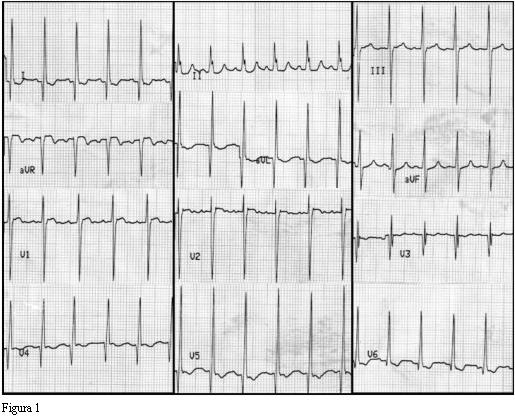

El ECG se muestra en la figura 1. Se observa un ritmo sinusal con una frecuencia de 136 latidos por minuto, siendo el rango normal para la edad entre 110-180 latidos por minuto. Ondas P e intervalo PR normales.

La duración del QRS está prolongada a expensas de su sector terminal. Mide 110 ms y lo máximo normal a esta edad es 80 ms. El eje eléctrico medio del QRS en el plano frontal está a 10 grados, siendo el valor normal a esta edad entre 10 y 120 grados. Presenta una onda S en V1 de 22 mm, para un máximo normal de 15 mm. Una onda R en V5 de 30 mm, para un máximo normal de 20 mm. La relación R/S en V1 es de 0,4, siendo el mínimo normal a esta edad 1. El voltaje de la onda R de V1 es menor que el voltaje de la onda R de V6, a la inversa de lo normal (1). Todos los signos anormales del QRS mencionados son comunes a muchas cardiopatías congénitas y adquiridas que determinan sobrecarga o dilatación del ventrículo izquierdo.

Continuando con el análisis de la morfología del QRS se observan ondas Q muy profundas en las derivadas izquierdas DI, aVL y de V3 a V6. Este hecho podría sugerir el diagnóstico de infarto ántero-lateral extenso, patología que no suele plantearse a esta edad. A los 3 meses de edad, y en el contexto de una miocardiopatía con esta evolución, es muy sugestivo de origen anómalo de la arteria coronaria izquierda. Con ese diagnóstico presuntivo, basado en el ECG, se procedió a avanzar en su estudio.

El ECG presenta signos de isquemia y/o infarto anterolateral en más de 80% de los casos. Las ondas Q mayores de 3 mm de profundidad y de 30 ms de duración en D1, aVL, derivaciones precordiales izquierdas y las alteraciones del segmento ST son signos muy sensibles y específicos de esta enfermedad (4).